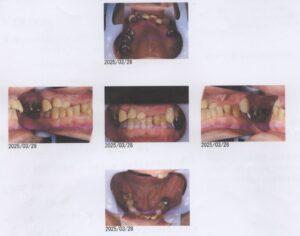

62歳男性

Underbite, crumbling teeth, orthodontics

咬合高径をあげれば受け口が改善される

ただし、奥歯には補綴が必要になる